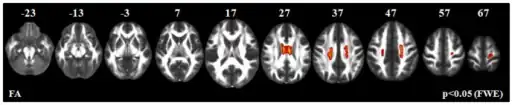

Genetics

Juvenile Primary Lateral Sclerosis is inherited in an autosomal recessive pattern, which means two copies of the gene in each cell are altered. Most often, parents of affected individuals each carry one copy of the altered gene, but do not show any signs or symptoms.

Mutations in the ALS2 gene, found on Chromosome 2, are responsible for causing Juvenile Primary Lateral Sclerosis. The ALS2 gene provides instructions for making a protein called alsin. Alsin is abundant in motor neurons, but its function is not fully understood. Mutations in the ALS2 gene in this disorder disrupt the instructions for producing alsin. As a result, alsin is unstable and decays rapidly, or it is disabled and cannot function properly. It is currently unknown how the loss of functional alsin protein causes the death of motor neurons and the symptoms of juvenile primary lateral sclerosis.[1]